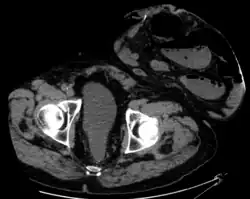

Placement of the stoma on the abdomen can occur at any location along the colon, but the most common placement is on the lower left side near the sigmoid where a majority of colon cancers occur. Other locations include the ascending, transverse, and descending sections of the colon.[4]